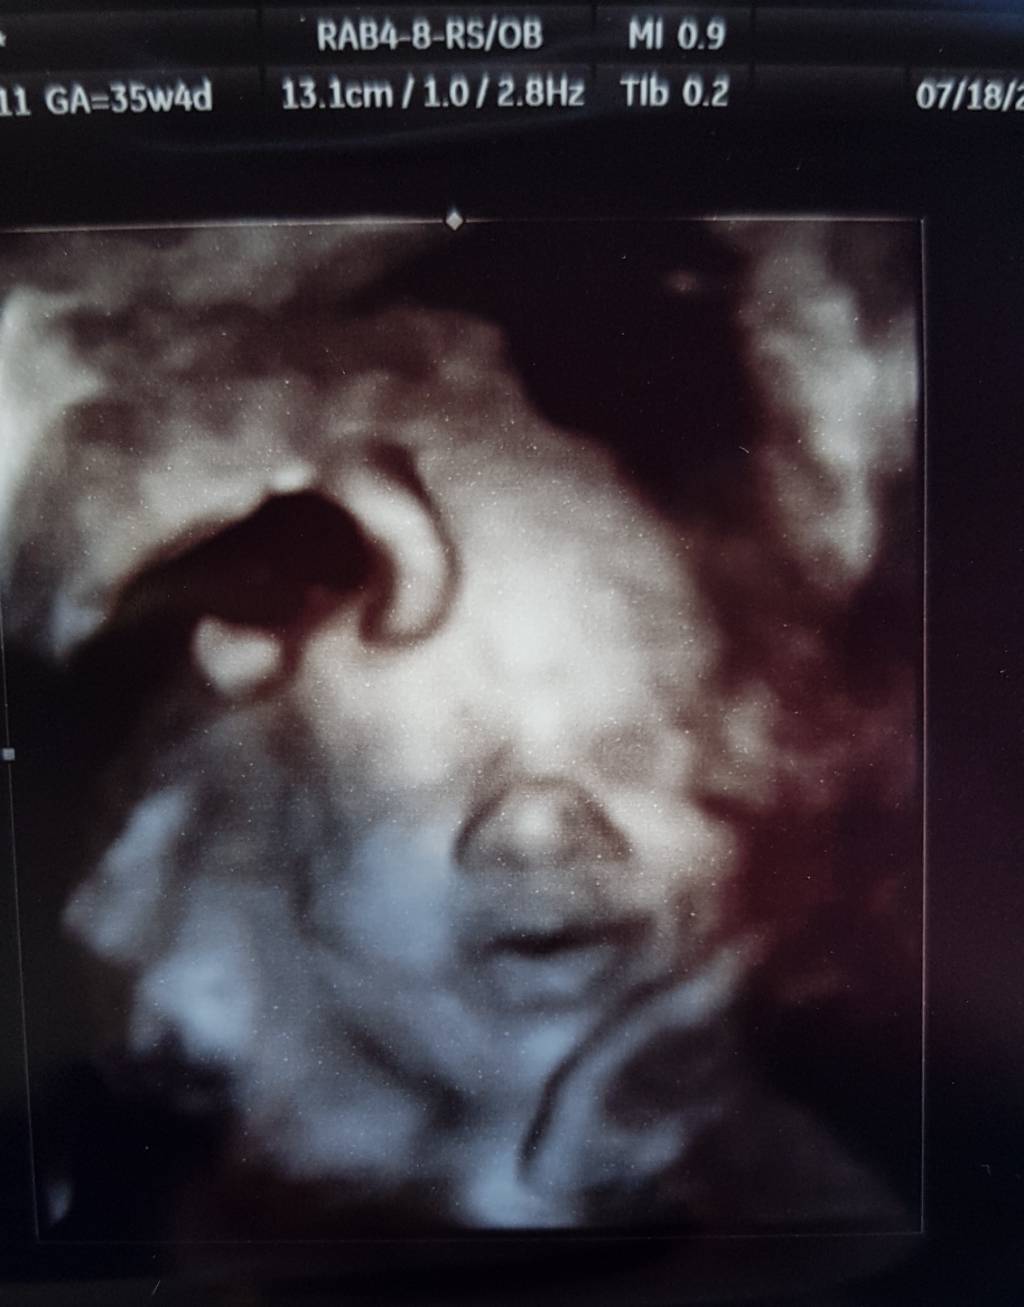

Zobacz załącznik 815200

A Michaś już jest taki duży